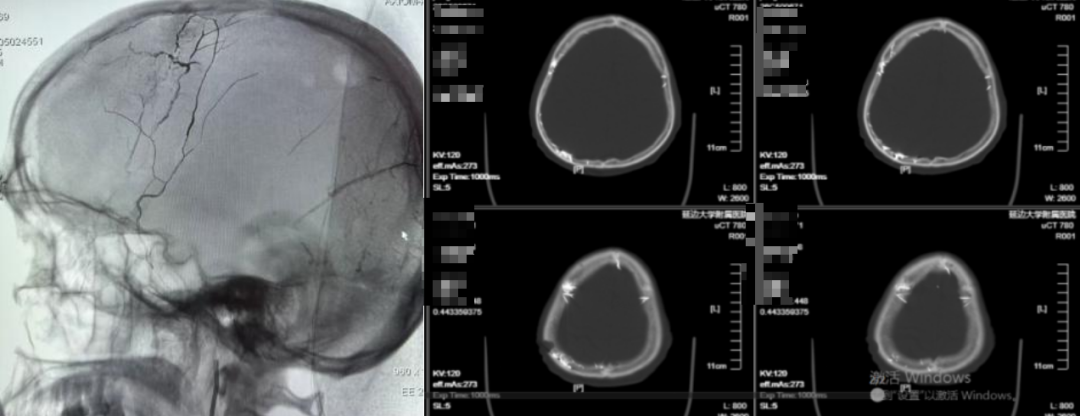

延边大学附属医院(延边医院)神经外科团队成功为近九旬高龄老人完成复杂颅内动脉瘤栓塞术